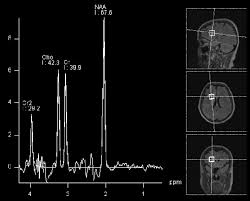

Brain Tumor Epidemiology Consortium Btec Ppt Download

Brain Tumor Epidemiology Consortium Btec Ppt Download from slideplayer.com